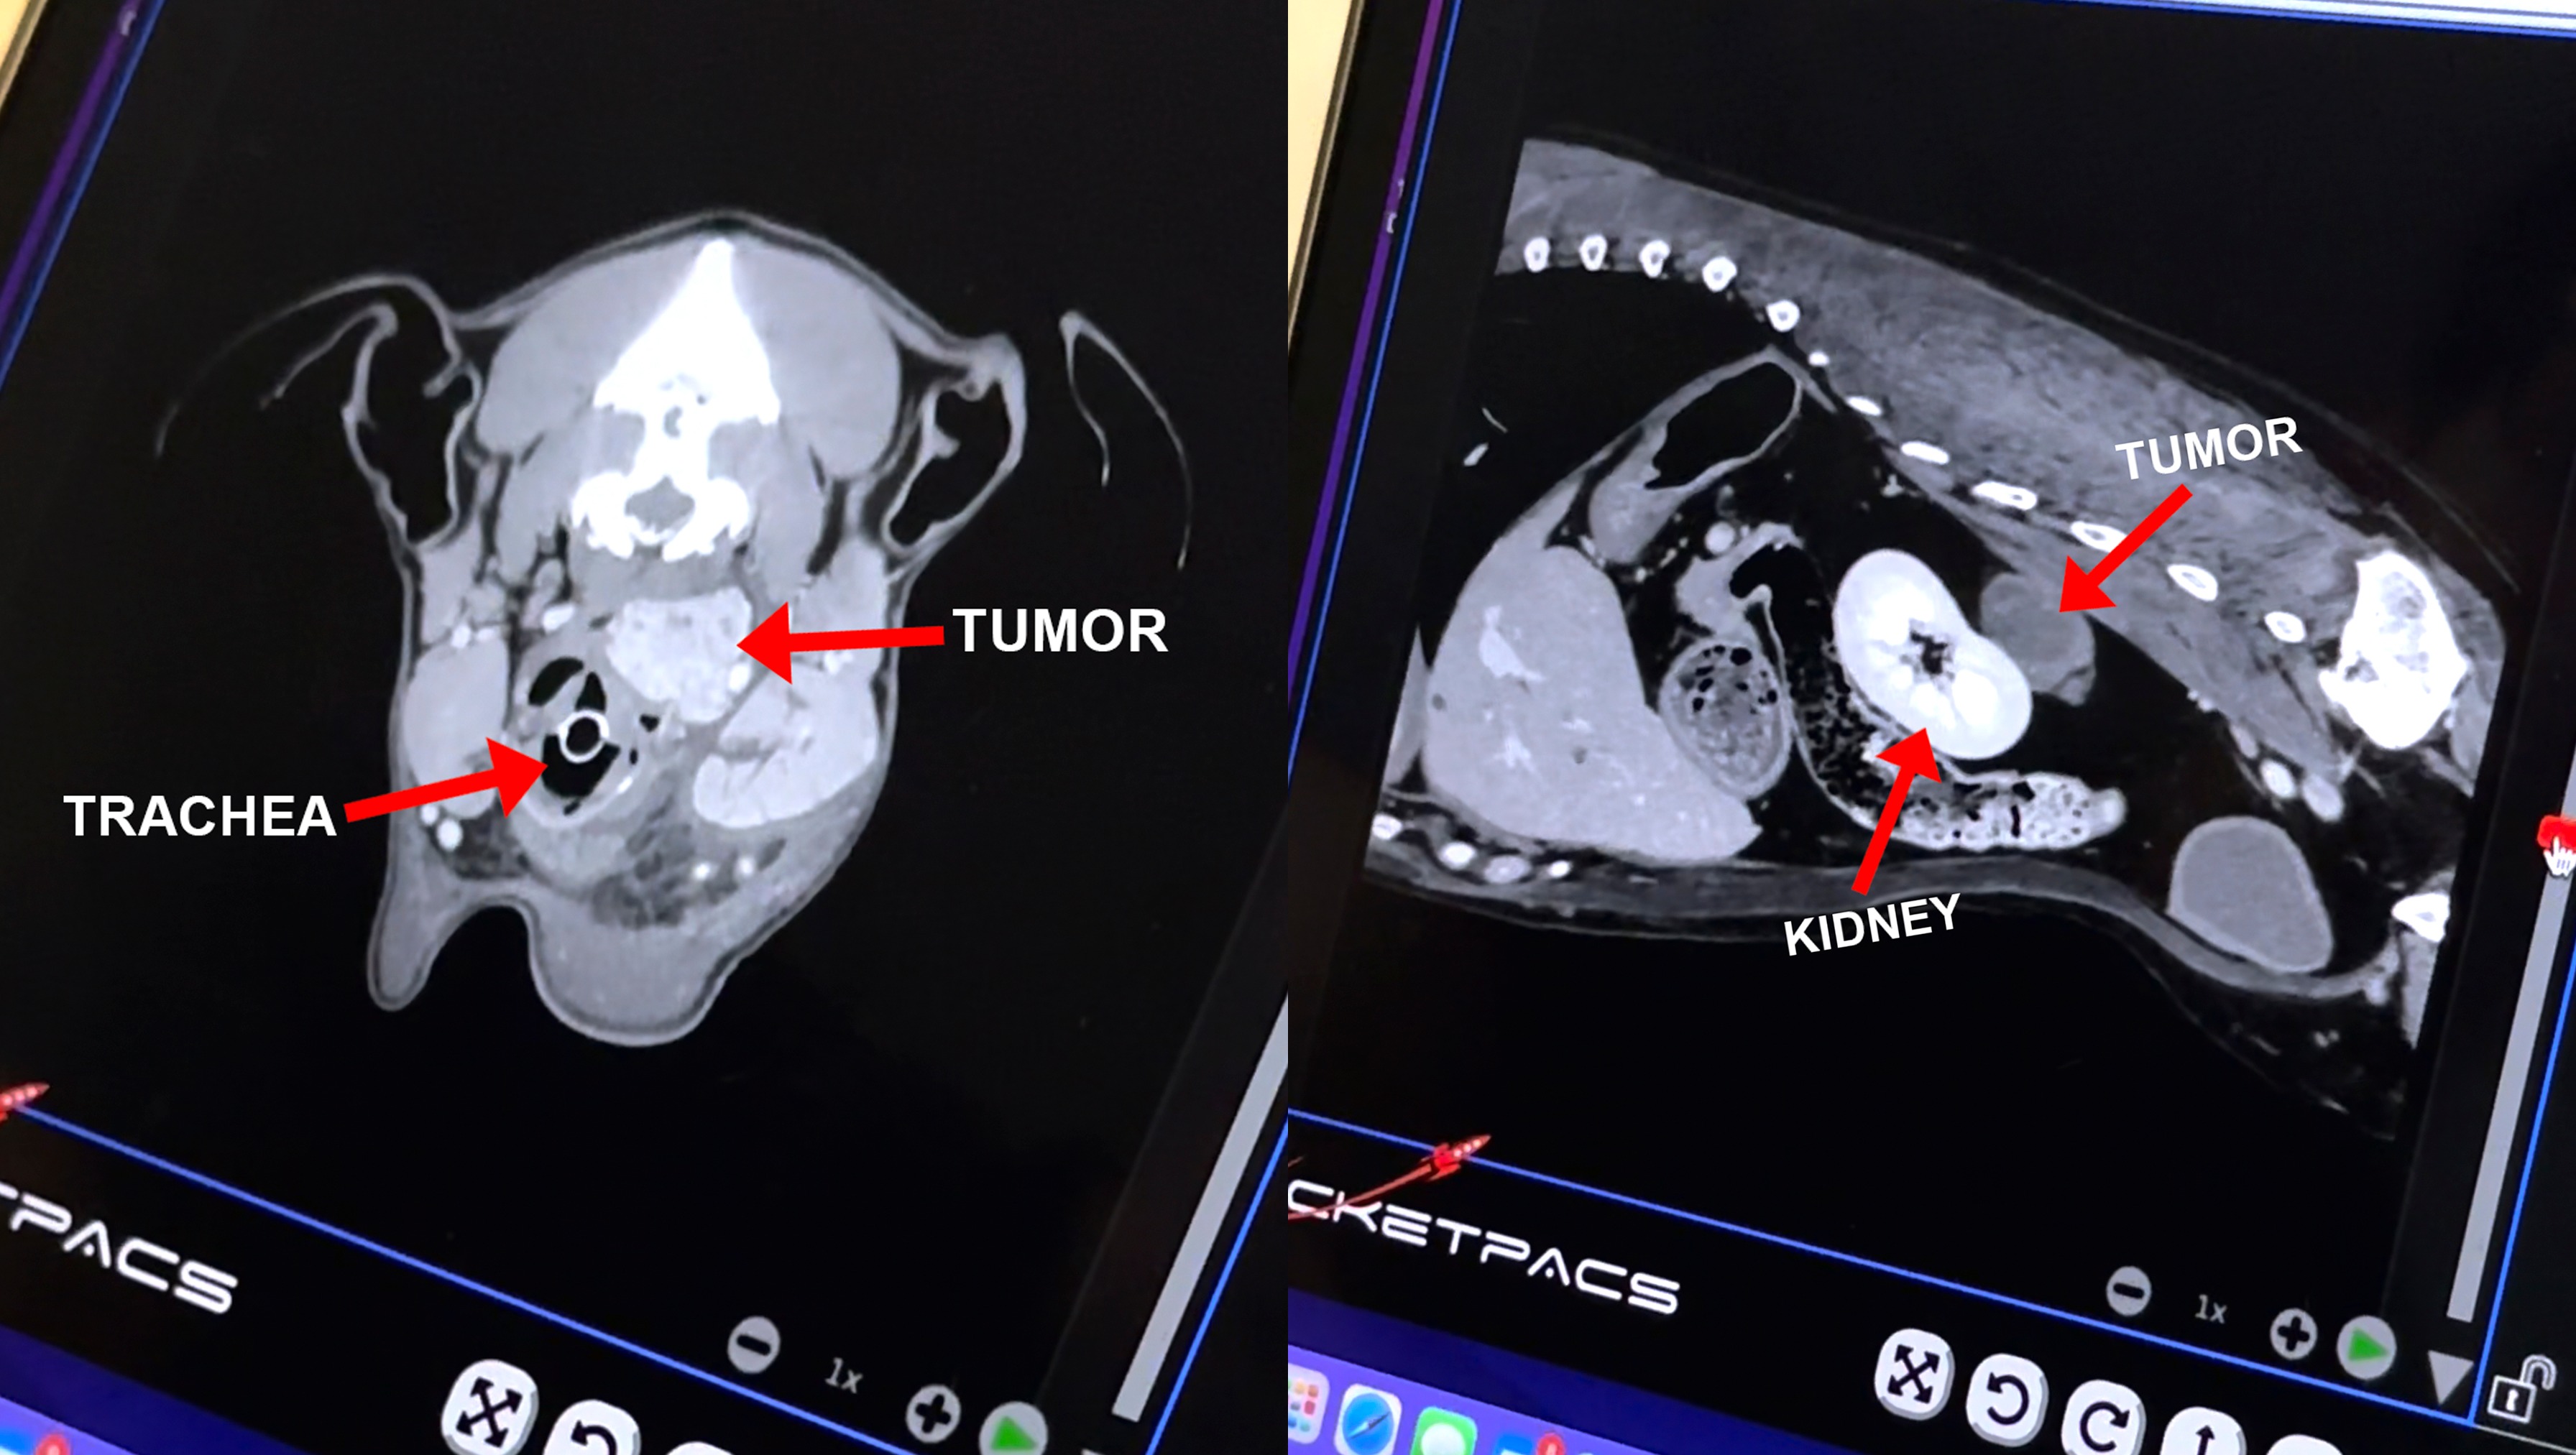

On July 18th I went to the hospital for a pre-operation visit for ACL knee surgery. Overnight I developed severe swelling in my neck. Several days of testing and hospital stays revealed I have a carotid body tumor pressing against my trachea (this makes it difficult for me to breath) and a tumor next to my kidney (that wasn’t there in February when I had an emergency splenectomy).

My mom and I have consulted with the brilliant oncologists at the Veterinary Cancer Group in Culver City and have landed on a course of radiation treatment to shrink both tumors starting August 3rd. We won't have results for a few months, but my mom and I are very hopeful!